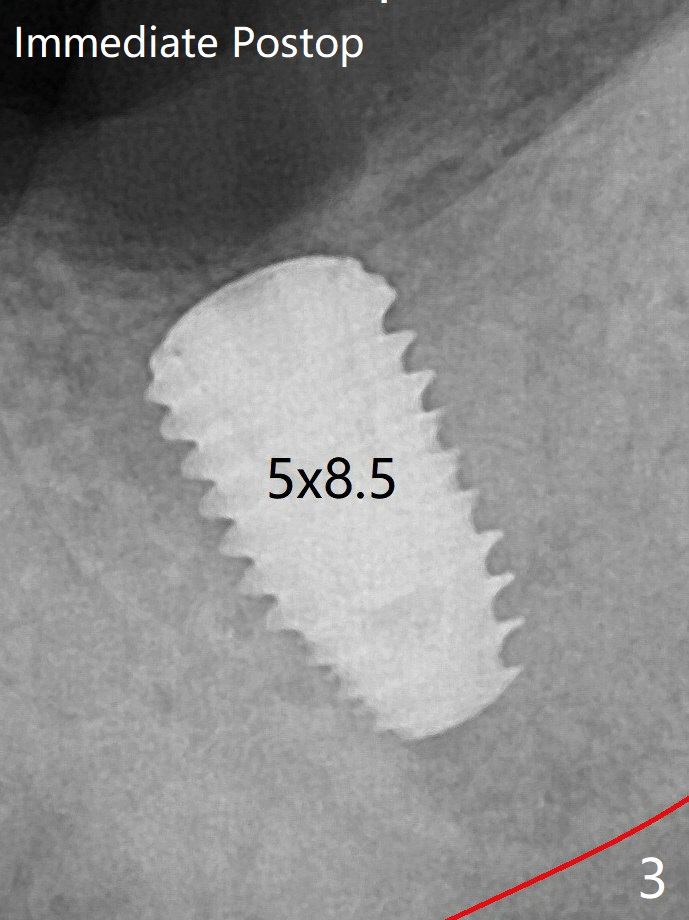

The bone is denser immediately next to the implant 3 months postop (Fig.8). A surgical bur has to be used to removed the bone coronal to the healing screw. 修复基台仿佛没有与牙槽嵴接触(图九)。调整基台高度后,取模。最后使用树脂水门汀粘固。